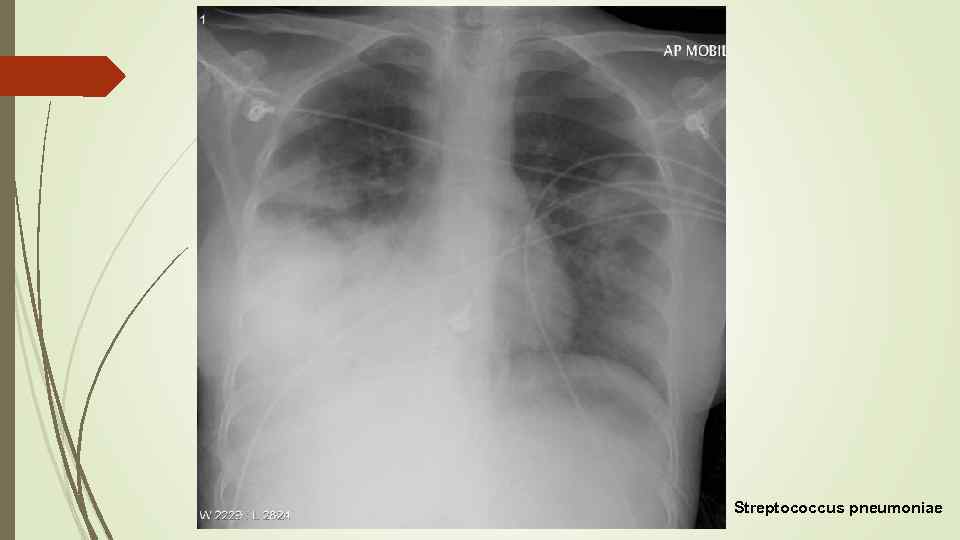

Streptococcus pneumoniae

Streptococcus pneumoniae